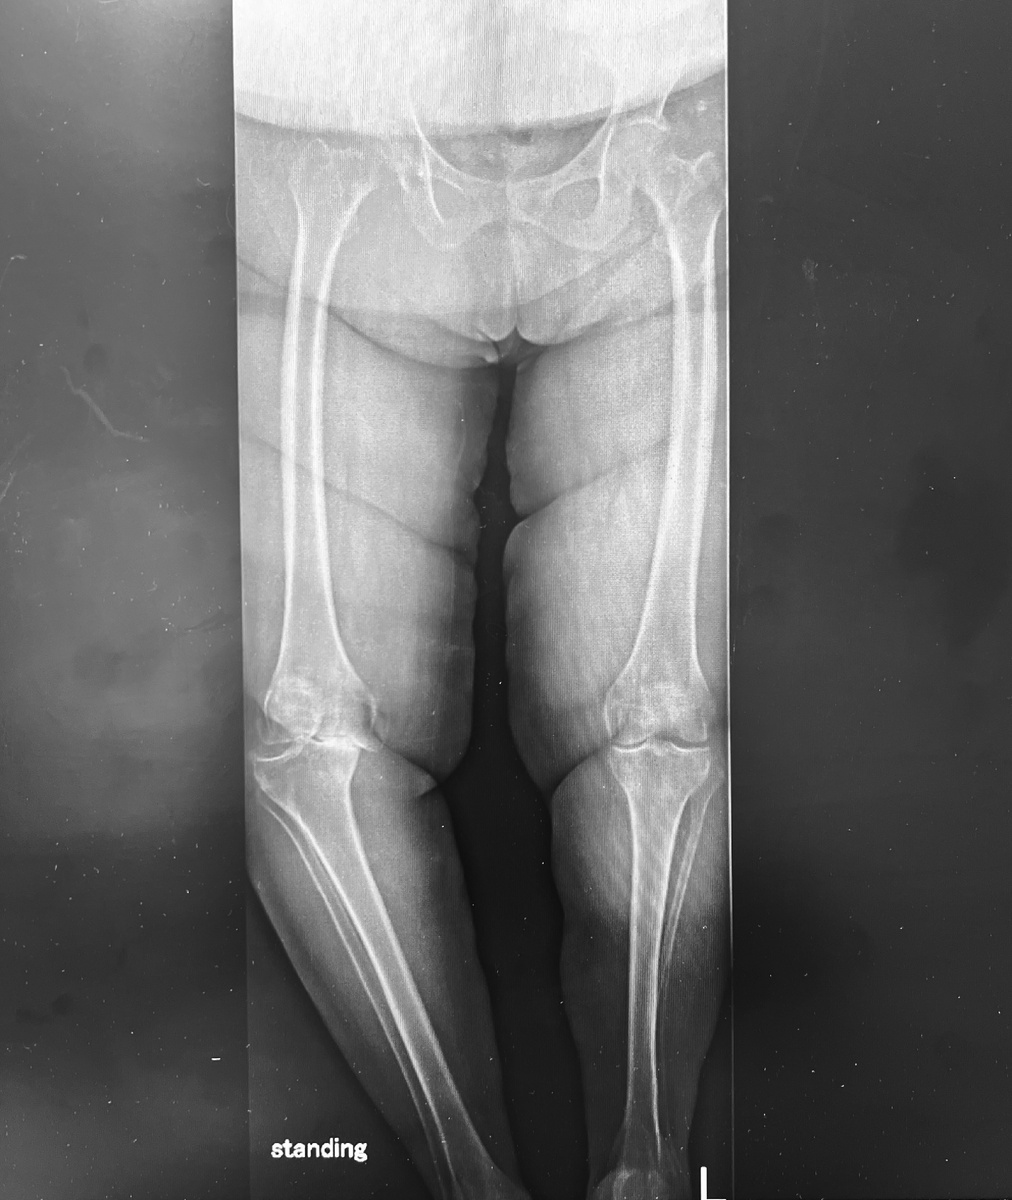

Чудесным образом несколько недель подряд оперировах Х-образные ноги, сегодня, наконец, традиционная О-образная деформация.

Очень выраженная.

Вот такая. Даже рентгенологом не нужно быть, чтобы увидеть разницу: относительно ровная левая нога, и очень деформированная правая. Всё это на фоне изрядного лишнего веса, заблокированного левого голеностопного сустава и деформированной правой стопы.